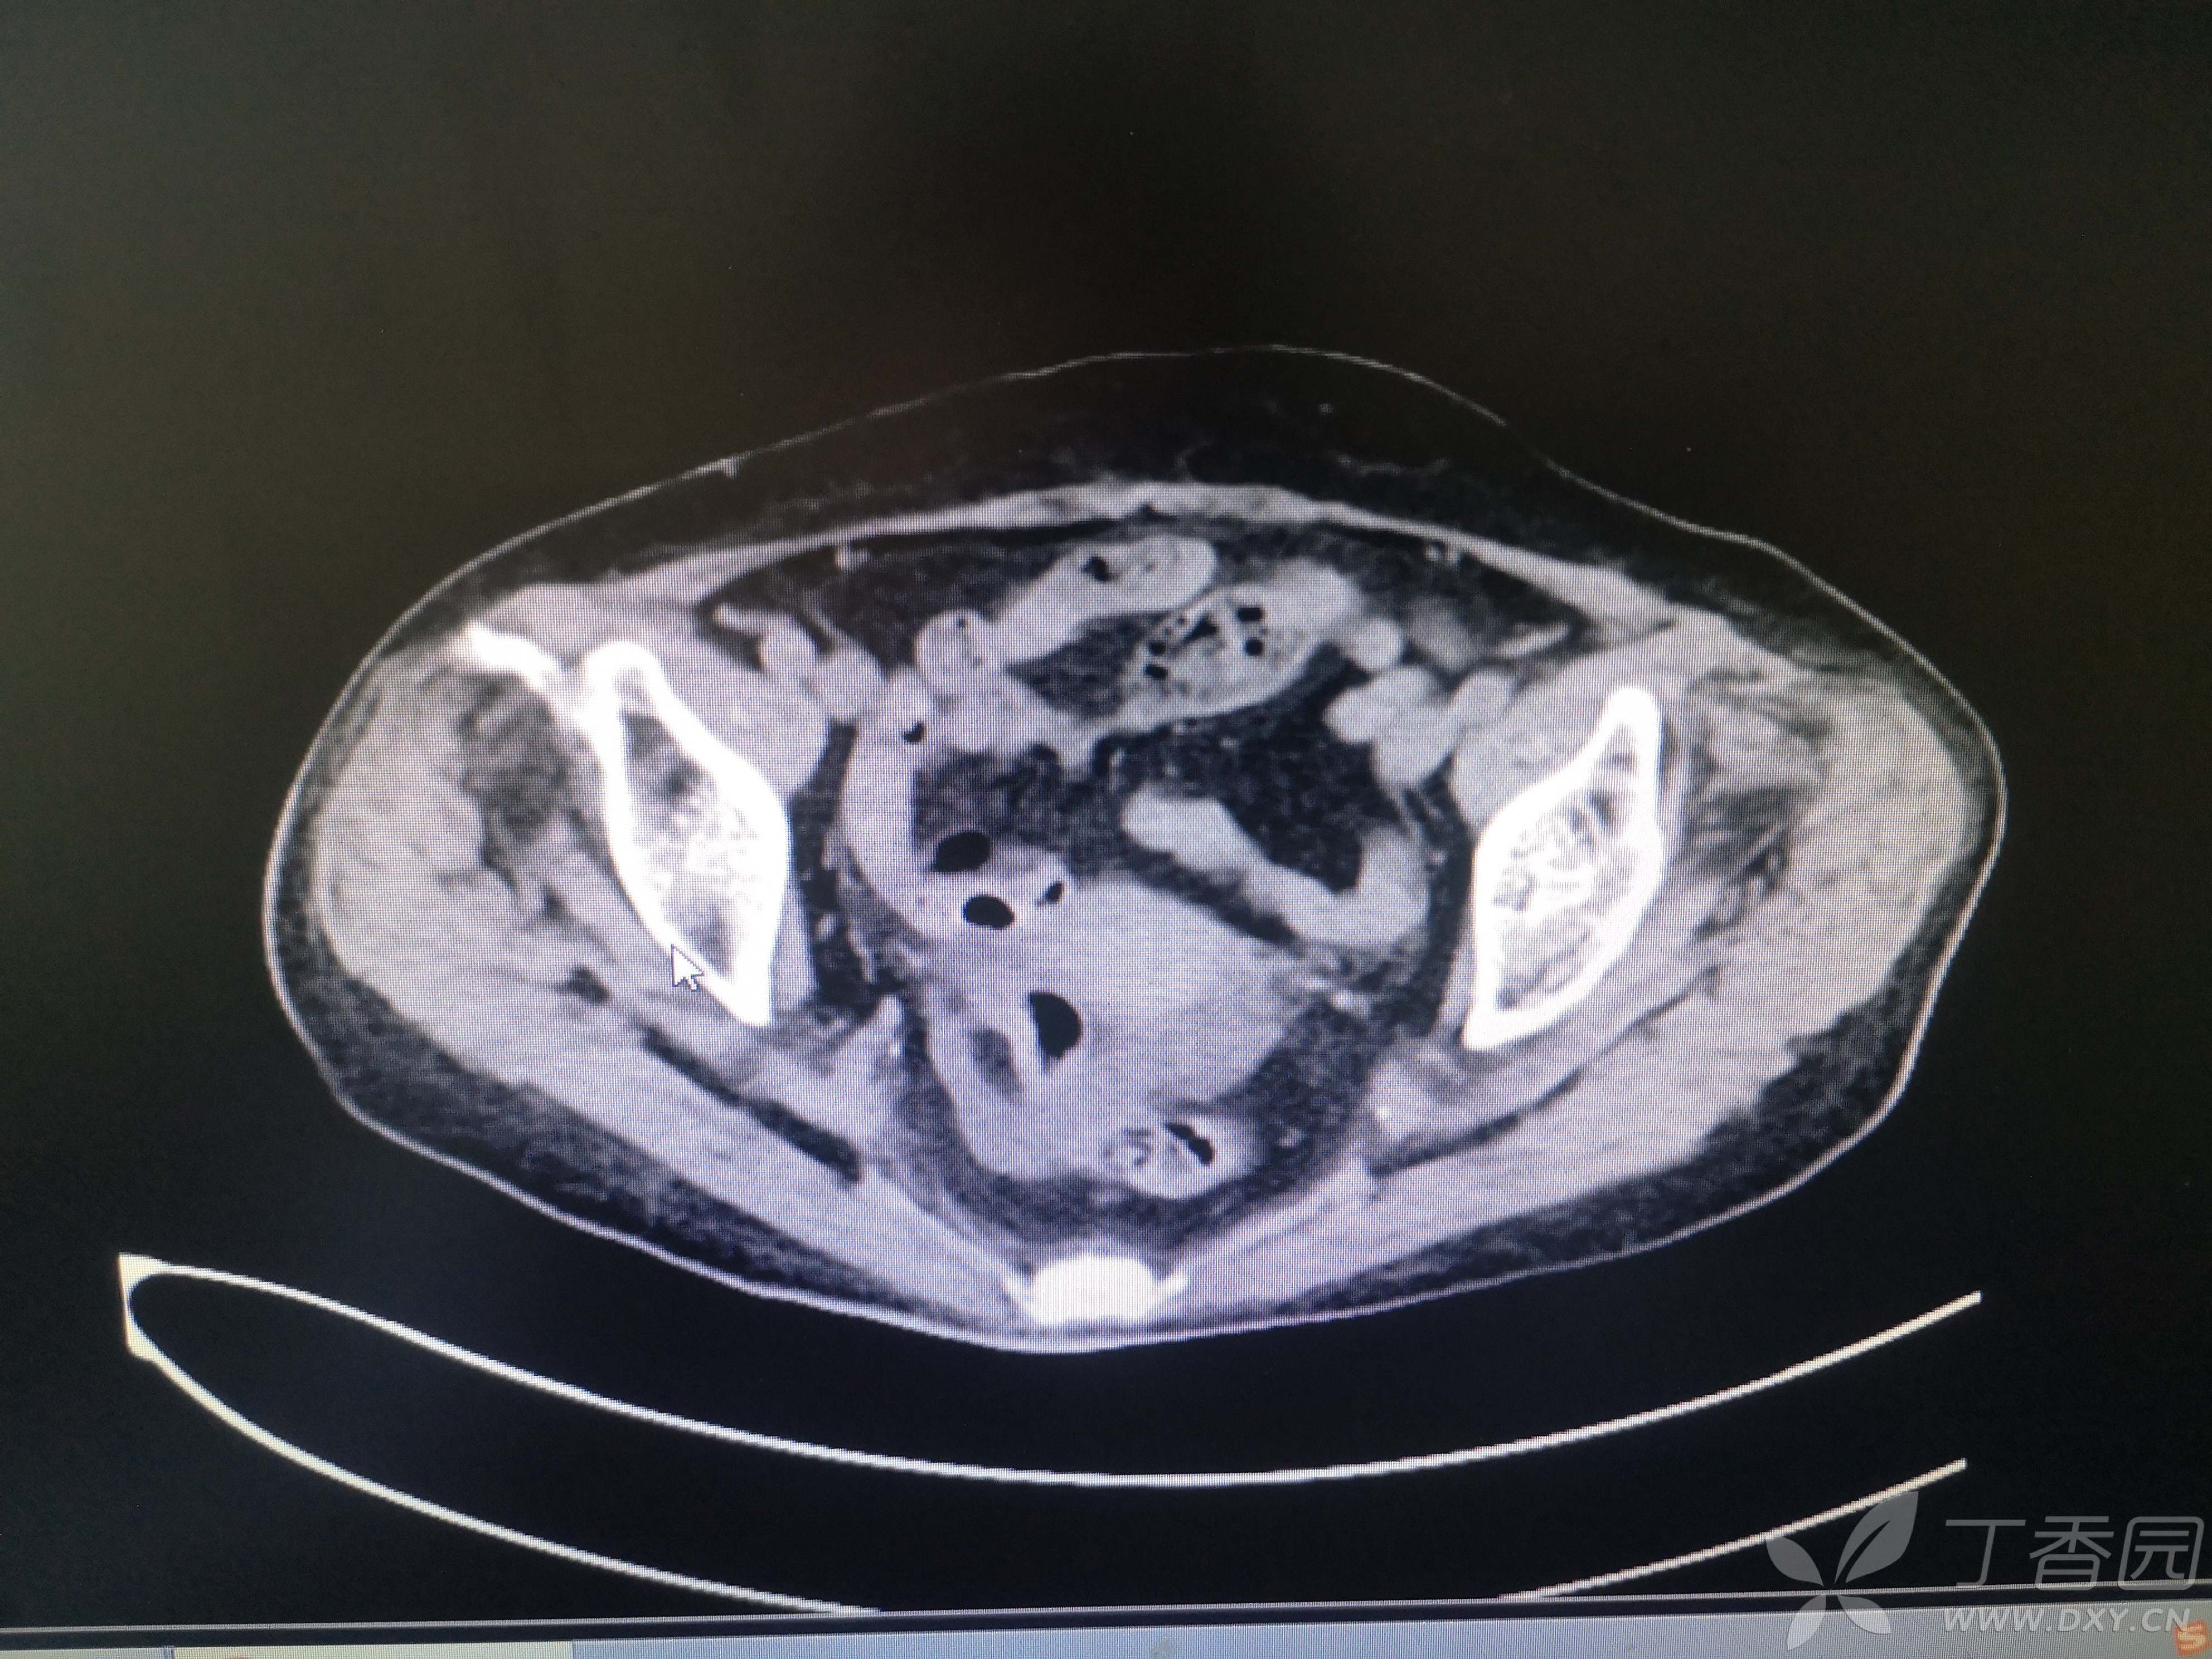

11小时前无明显诱因出现右腹部疼痛,伴恶心、呕吐,呕吐物清稀黏液,急至我院就诊,患者在家属搀扶下步入急诊室,神志清,言语费力,呼吸浅快,口唇、手足皮肤青紫,心电图示快速房颤,血压低至68/48mmHg,脉氧测不出,动脉血气分析PH 7.1,PCO2 13.6mmHg,PO2 135mmHg,Lac15.1mmol/L,HCO3 4.1mmol/L,K 6.11mmol/L。CT、血常规、血凝、生化等结果见图 。

患者CT图像如下

完善CT检查以后收入重症医学科治疗。

入院诊断1.感染性休克2.多器官功能衰竭(急性肝功能不全 急性肾功能不全 心功能不全 凝血功能障碍)3.急性胆囊炎4.电解质代谢紊乱5.代谢性酸中毒6.肺部感染7.心房颤动8.多发性肾囊肿9.冠心病10.盆腔积液。